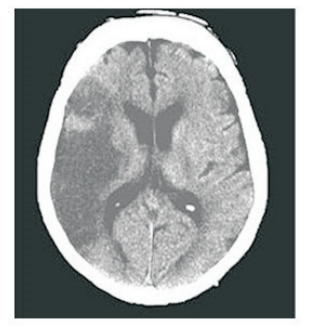

Paciente do sexo masculino, 65 anos, hipertenso e diabético, apresentou episódio súbito de hemiparesia em dimídio esquerdo. Foi solicitado Ressonância Magnética de crânio com a imagem a seguir.

Com relação à topografia da lesão vascular, a artéria afetada foi :